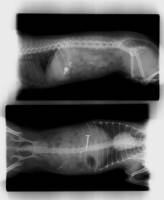

arrêt transit baryté chien dieppe

Les corps étrangers digestifs

L'ingestion de corps étranger est fréquente chez les carnivores domestiques. Les symptômes peuvent être très variés : vomissements aigues ou chroniques, diarrhée, absence de selles, douleurs abdominales plus ou moins marquées, traces de sang dans les selles, dysorexie ou anorexie totale, amaigri...